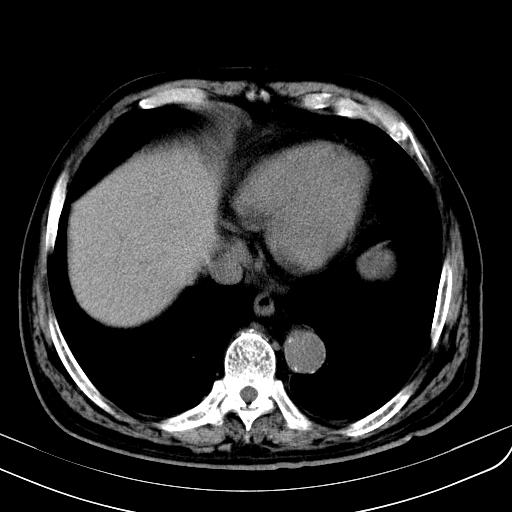

胃底靠近胃大弯处可见一圆形软组织影,直径为3.45cm,ct值约为30.1hu